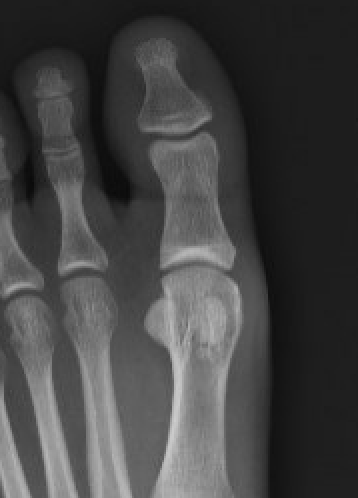

Xray

Enlarged / deformed / sclerotic with mottling / fragmentation

Management

Orthotics / activity modification / NSAIDS

Isolated sesamoid resection